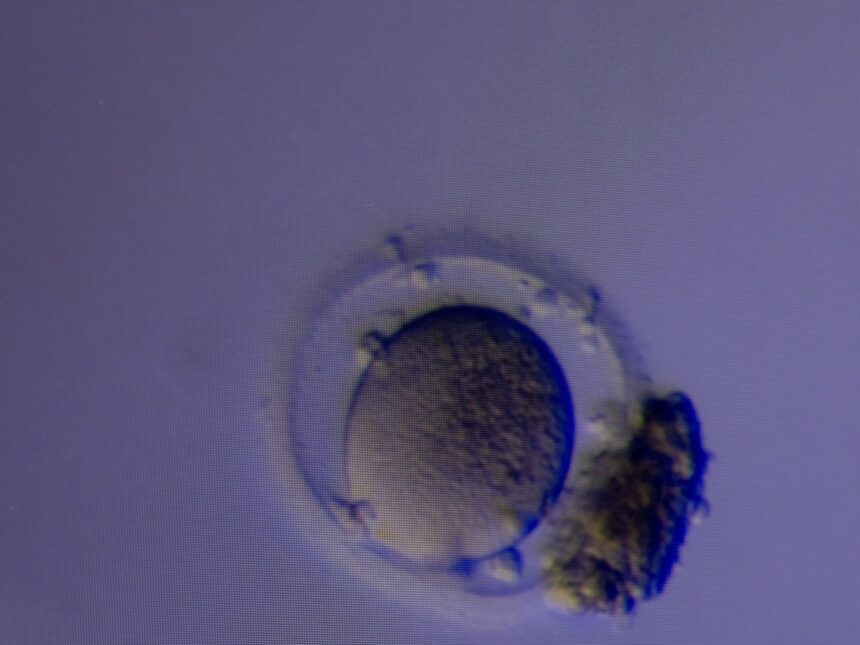

Parte del sistema OvaReady, utilizado para aislar y despojar los óvulos. Foto Cassandra Klos para The New York Times.

Parte del sistema OvaReady, utilizado para aislar y despojar los óvulos. Foto Cassandra Klos para The New York Times.Kapur afirmó que esperaba que algunas clínicas procesaran todo el líquido folicular de una paciente con el dispositivo, mientras que otras podrían adoptar un enfoque más conservador, analizando la mitad de la muestra con OvaReady y examinando la otra mitad de forma convencional antes de analizarla con el dispositivo.